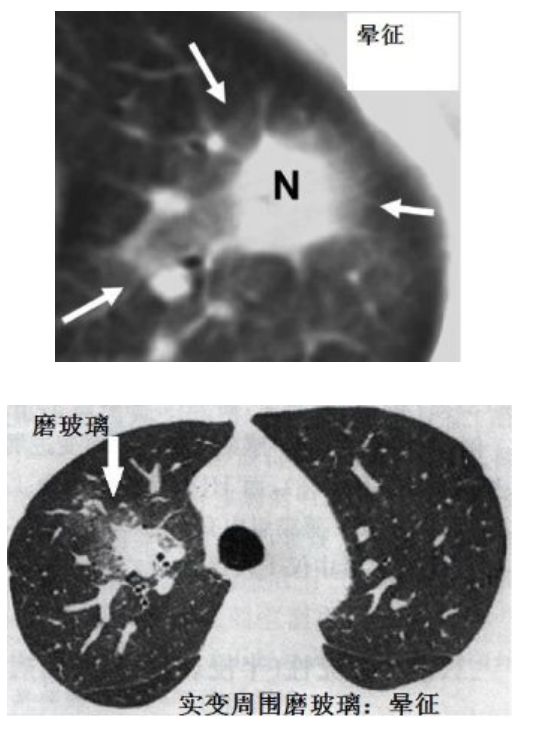

▎晕征和反晕征

有学者看到下面这张CT说这是晕征,我没有看出来晕征,只看出头晕,我感觉我要去看眼科。

图14

下面这个才是晕征(看得见的那种),不过这个是肺曲霉病的晕征。

图15

下面这个有学者说这是反晕征,我没有看出来反晕征(正着、反着看都没有看出来),我又看出头晕了~有哪位高手可以指点?

图16

这个隐源性机化性肺炎患者的CT,才是典型的反晕征。

图17

很多疾病都会出现晕征和反晕征,但是有一点,普通的肺炎很少出现晕征和反晕征,这对鉴别新冠肺炎还是比较有价值的。